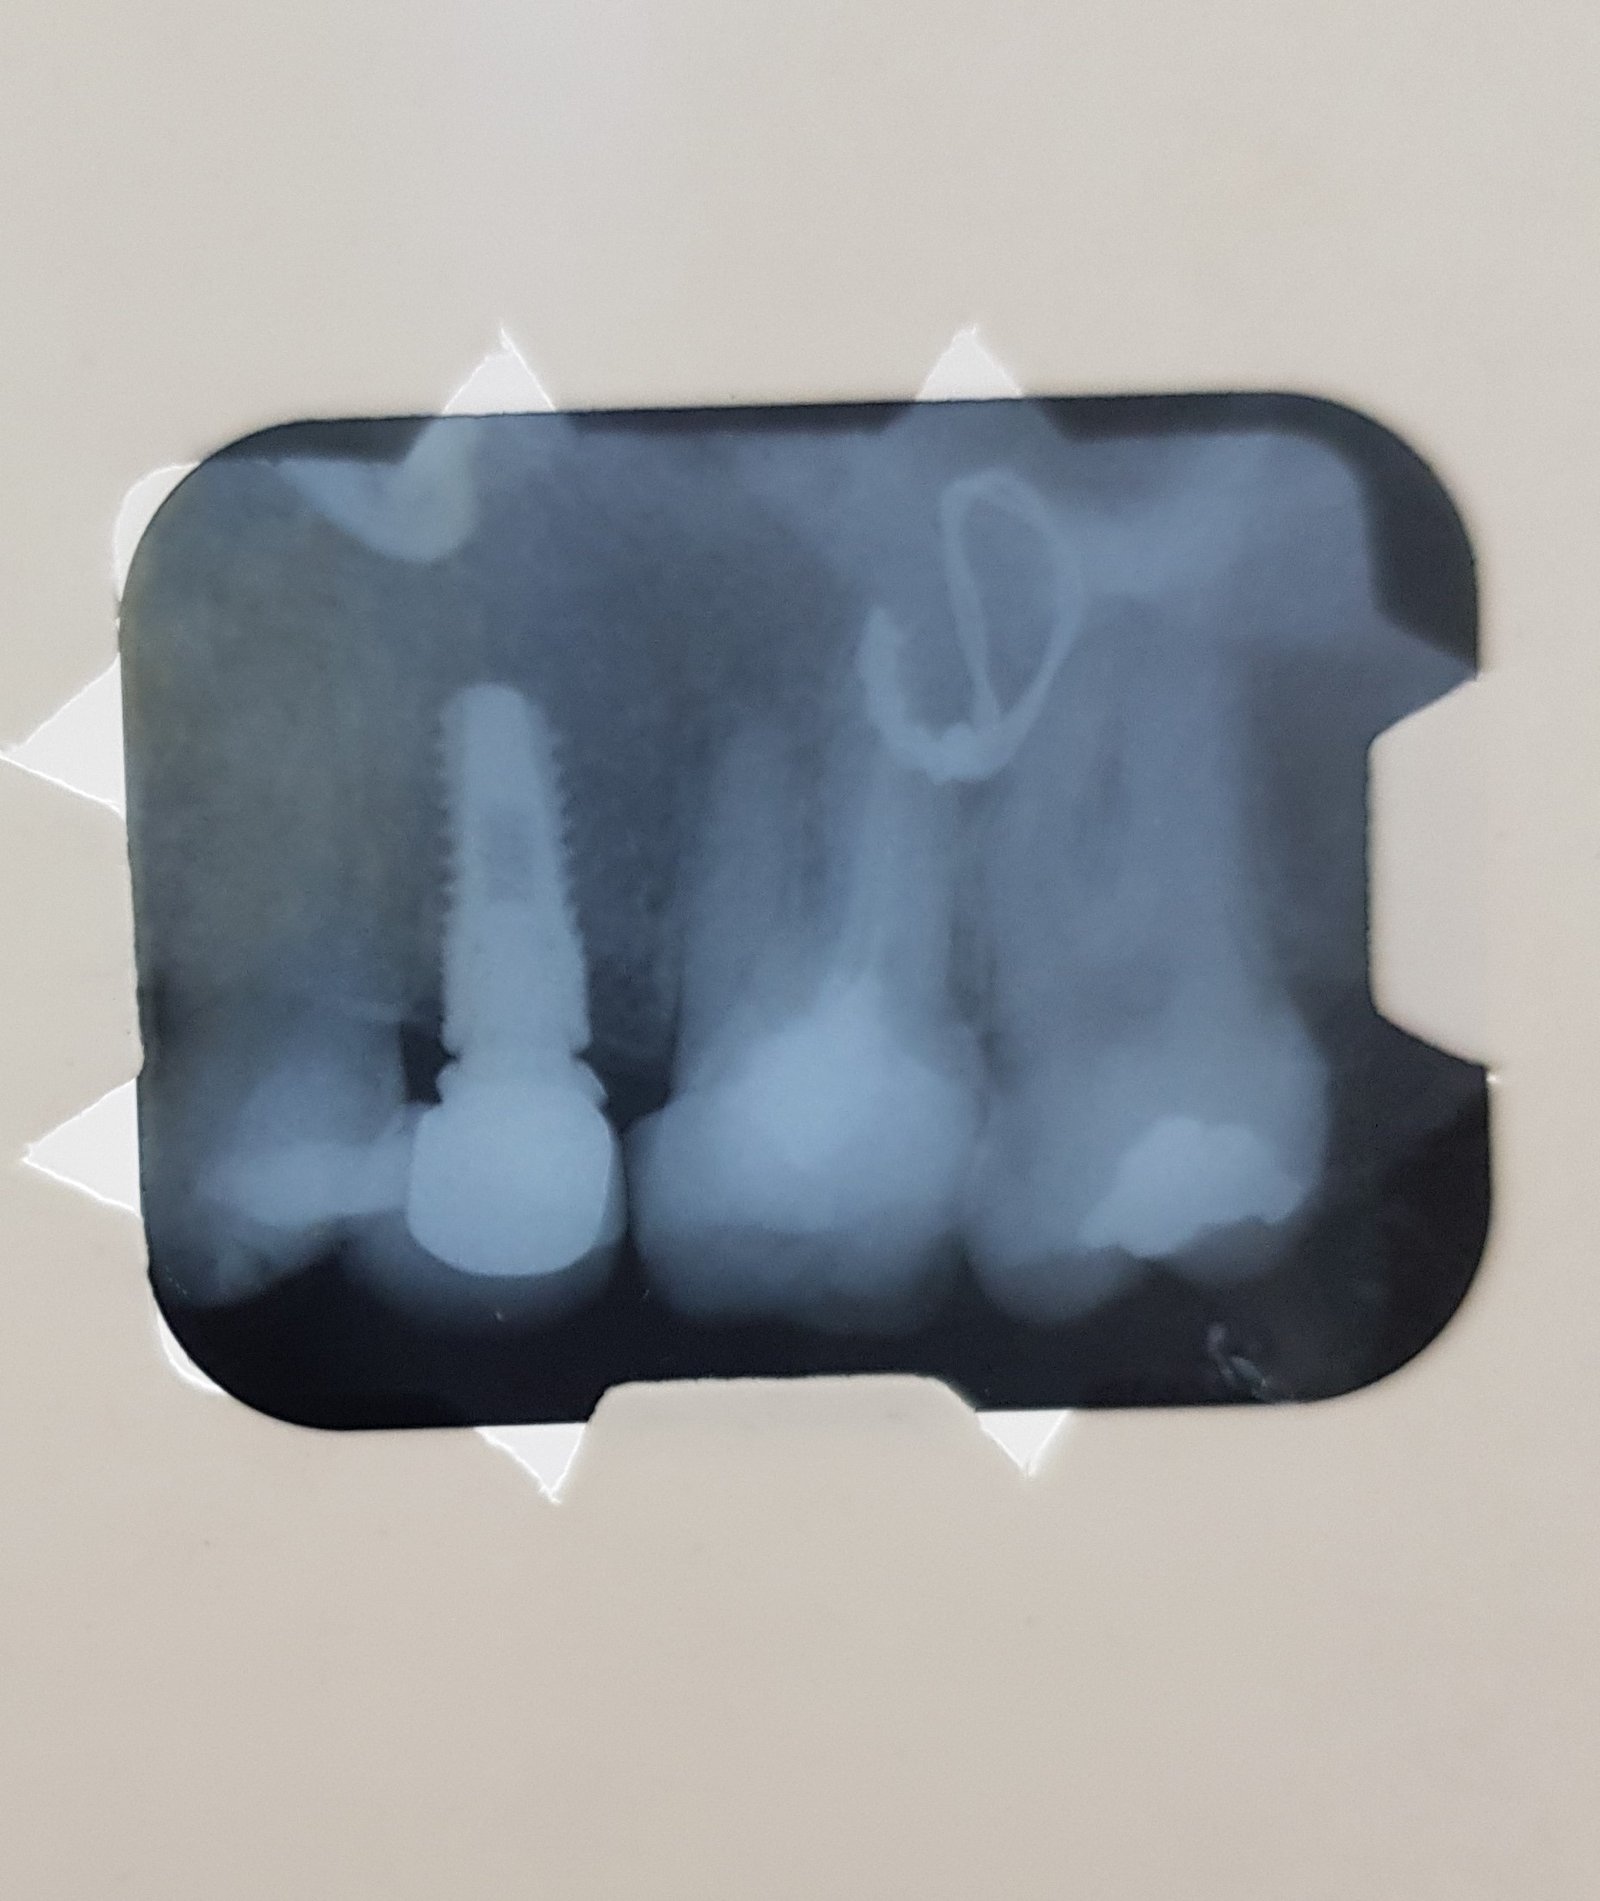

Buenos días, necesito ayuda con los implantes 36 y 46, necesito cambiar las coronas de ambos y no se que implantes son.... lo único que sabemos es que fueron colocados [...]